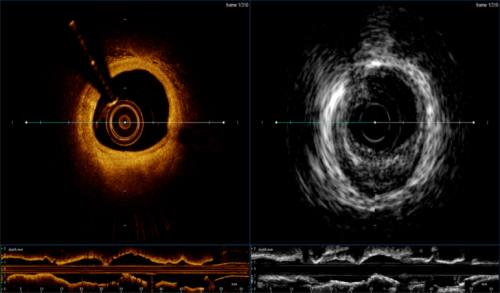

本次獲得注冊(cè)證的血管內(nèi)成像設(shè)備及導(dǎo)管是由全景恒升(Panovision)和哈爾濱醫(yī)科大學(xué)附屬第二醫(yī)院于波教授團(tuán)隊(duì)共同研發(fā),這是一款將現(xiàn)有IVUS,OCT兩項(xiàng)技術(shù)融合的新一代腔內(nèi)影像機(jī)器及導(dǎo)管,產(chǎn)品擁有智能的算法平臺(tái),突破性的探頭融合技術(shù)和優(yōu)異的圖像質(zhì)量,提供一系列多模態(tài)的成像方式和臨床診斷影像學(xué)解決方案,旨在幫助術(shù)者全面準(zhǔn)確獲取管腔IVUS,OCT信息,助力術(shù)者實(shí)現(xiàn)精準(zhǔn)醫(yī)療。

S1配備手動(dòng)和自動(dòng)測(cè)量管腔面積、直徑、長(zhǎng)度且提供智能支架和管腔輔助探測(cè)功能,輔助分析支架貼壁不良,專業(yè)直觀的軟件界面設(shè)計(jì),實(shí)現(xiàn)各種功能一鍵切換,盡享絲滑;配備三種類型的成像模式,醫(yī)師可選擇IVUS,OCT雙模水平視圖或重疊融合視圖,也可選擇單模成像,此外血管三維重建體渲染技術(shù)提供了360度全方位觀察視角并且可多角度旋轉(zhuǎn)拉伸,讓臨床醫(yī)師從多維度觀察病變。

作為冠狀動(dòng)脈介入診療中最主要的兩種血管腔內(nèi)影像學(xué)技術(shù),兩種影像學(xué)技術(shù)已成為心血管介入醫(yī)生不可或缺的輔助手段,其自身都有一定的優(yōu)勢(shì)和缺陷,OCT具有更高的分辨率,能更好地分析斑塊成分,但是穿透深度有限;IVUS具有更強(qiáng)的穿透力,能夠更深層的成像,但空間分辨率較弱。